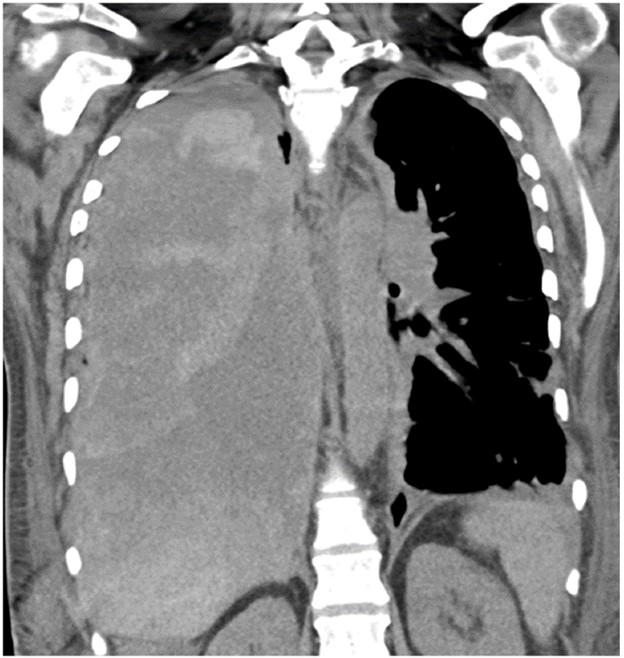

Acute rejection can occur anytime after lung transplant. It consists of two types, acute cellular rejection (ACR) and antibody-mediated rejection (AMR), which can coexist. ACR is the more common of the two types and occurs when recipient T lymphocytes attack donor antigens within the lung allograft. Approximately 35% of lung transplant recipients experience at least one episode of ACR during the 1st year after transplant [2]. During these episodes, patients may be asymptomatic or may present with nonspecific symptoms such as dyspnea and cough. The imaging findings of ACR are nonspecific and include consolidation, ground-glass opacities, and septal-line thickening; as with hyperacute rejection, ACR resembles pulmonary edema. Given its nonspecific clinical and imaging manifestations, ACR requires transbronchial biopsy and tissue analysis for diagnosis. Timely treatment, typically by increased immunosuppression with steroids, is important because ACR is the greatest risk factor for chronic lung allograft dysfunction [4]. Figure 1 shows a patient with biopsy-proven ACR.

AMR, the less common of the two types of acute rejection, occurs when recipient B lymphocytes create donor-specific antibodies (DSA), donor-specific antigens and DSA form complexes, and the complexes trigger the immune system’s complement pathway. Like patients with ACR, patients with AMR can be asymptomatic; can have nonspecific symptoms such as dyspnea and cough; and can have normal chest imaging or nonspecific imaging findings resembling pulmonary edema such as consolidation, ground-glass opacities, and septal-line thickening. Transplant physicians diagnose patients with clinical versus subclinical AMR and definite versus probable versus possible AMR on the basis of the presence or absence of allograft dysfunction, histology results suggestive of AMR (such as neutrophil arteritis and capillaritis), immunostaining results (positive C4d staining of the capillary endothelium), and the presence or absence of DSA in peripheral blood [4]. Treatments include plasmapheresis and IV immunoglobulin to remove harmful antibodies and to suppress antibody production, respectively. Steroids are not typically used to treat AMR, unlike ACR. Figure 2 shows a patient with AMR.

Fig. 2—Patient with history of bilateral lung transplant who developed antibody-mediated rejection (AMR), which was diagnosed by transbronchial biopsy and donor-specific antibody blood testing. Chest CT at time of AMR diagnosis shows ground-glass opacities and reticulation in both lungs and small pleural effusions.